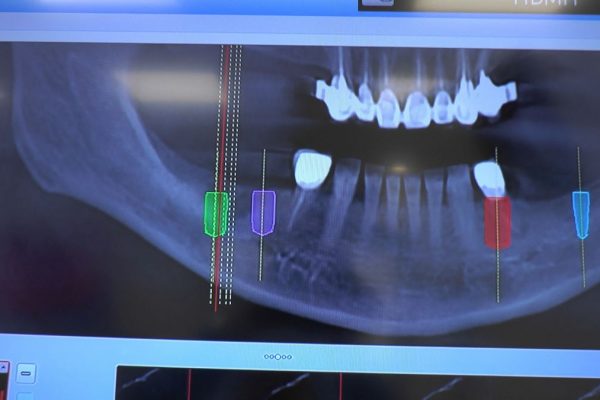

W ostatni weekend czerwca 2018 roku kursanci II Sezonu Preludium Implantologii odbyli piątą, finałową sesję, która w całości podporządkowana była praktyce. W ciągu dwóch dni zabiegowych Lekarze uczestniczący w szkoleniu przeprowadzili szereg zabiegów pod kierunkiem dr n.med. Violetty Szycik. Wszczepili 17 implantów oraz przeprowadzili ekstrakcje i zabiegi regeneracyjne kości. Zabiegi były wykonywane także w sedacji dożylnej z udziałem specjalisty anestezjologii i intensywnej terapii dr Jolanty Grzybowskiej. Preludium implantologii to nowy program edukacyjny dla adeptów implantologii stomatologicznej, którego celem jest wprowadzenie do implantologii poprzez pozyskanie wiedzy w szerokim zakresie i uwzględnieniem szczegółów mających decydujące znaczenie dla powodzenia leczenia implantologicznego. Ale tak jak wszystkie szkolenia w Instytucie Vivadental, w tym wiodące Practiculum Implantologii, zorientowane jest na praktyce i samodzielnym wykonywaniu zabiegów pod kierunkiem Mentora. To najlepsza edukacja w medycynie zabiegowej, a zarazem najlepszy start do implantologii.